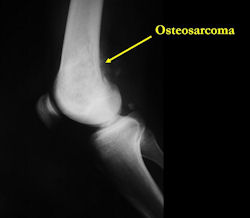

Xray (plain radiographs) of the extremity

There are 3 radiographic presentations for osteosarcomas, depending upon the amount of osteoid/ossification and calcium deposition:

Conventional osteosarcomas are permeative lesions on plain radiographs (borders of the lesion cannot be clearly delineated)

- Most (90%) arise from the metaphysis of the bone

- Rarely (10%) arise from the diaphysis